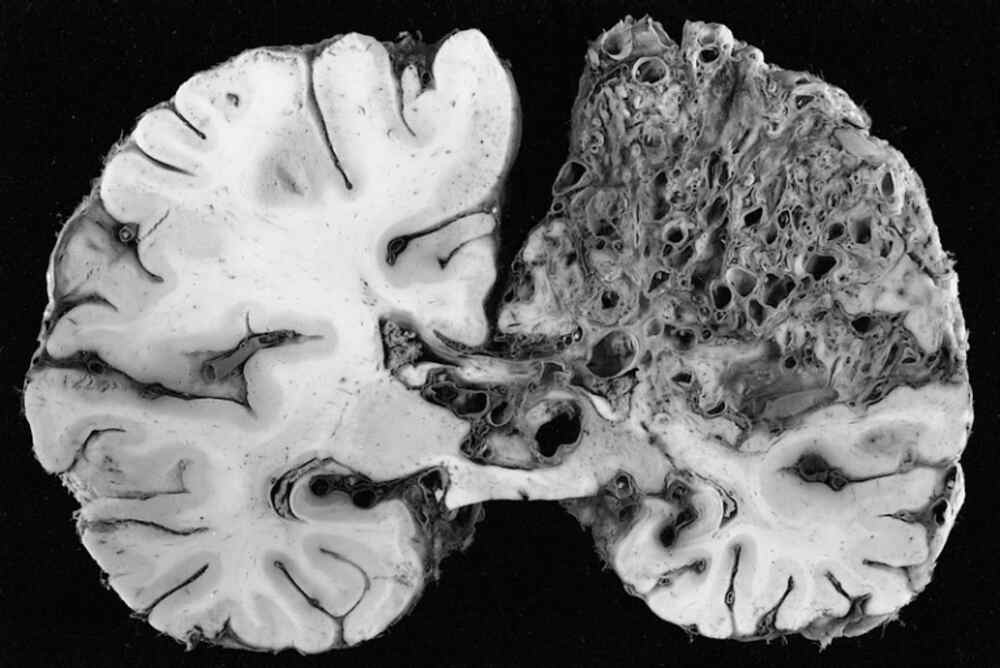

What is a Brain AVM?

A brain Arteriovenous Malformation (AVM) is an uncommon abnormal cerebral blood vessels. It interferes with normal blood flow through direct connections between veins and arteries that bypass the vital capillary system. This condition causes high-pressure blood flow in weak vessels, which are more prone to rupture. If untreated, the AVMs in the brain pose serious risk to health as the weak vessels can rupture in a way that could cause bleeding within the brain (hemorrhage) or stroke or irreparable neurological damage. Early diagnosis and treatment in a specialist AVM hospital such as IRFacilities are vital to prevent these serious problems and maintaining the neurological function.

There is no evidence of cause of this condition that is not a result of environmental or lifestyle factors. Thus, the diagnosis is crucial and heavily depends on the area that is AVM Radiology. Modern imaging techniques such as MRI as well as CT angiography are employed to precisely determine the size of the malformation and location as well as pattern of flow. The precise radiological assessment is vital for precise guidance in subsequent treatment plans and to ensure a safe treatment strategy.